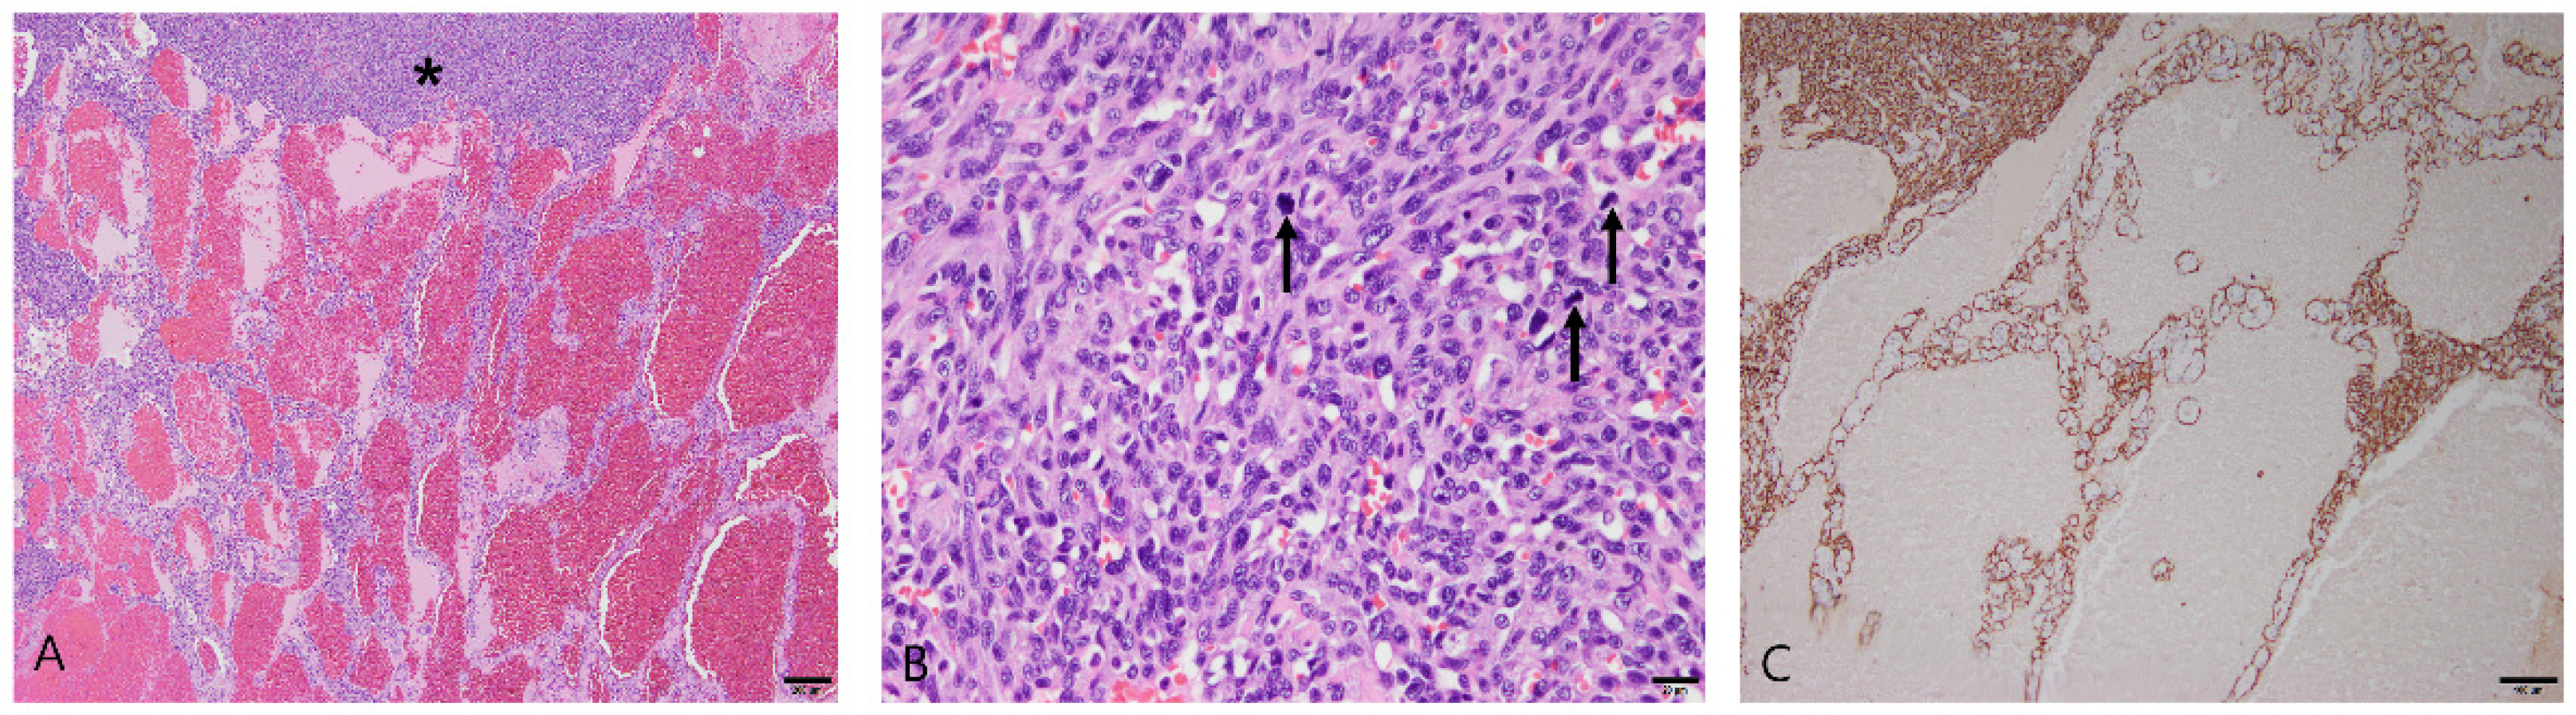

3.2.3. Splenic Hemangiosarcoma

3.2.4. Splenic Lymphoma

3.2.5. Stromal Sarcomas